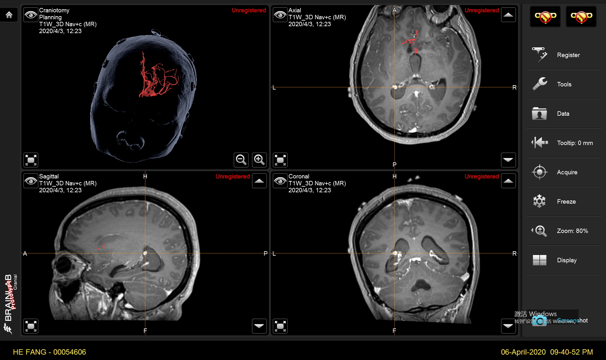

手术计划

手术方案A:动脉瘤栓塞联合低流量搭桥。

手术方案B:动脉瘤切除联合低流量搭桥。

备选方案:

脑室内血肿清除+动脉瘤切除+低流量搭桥。

与其他可用于深部动脉瘤治疗的微创方法相比,endoport辅助显微外科具有一定的优势。首先,endoport的优势是微创:皮层造瘘中,endoport的光面结构能有效地减少造瘘通道皮层的挫伤,从而减少了对脑组织的继发损伤。其次皮层造瘘口稳定,减少了人为使用脑压板过程中造成的造瘘口撕裂。然而endoport也存在相应弊端[7],钙化病变和直径大于3厘米的病变可能难以通过endoport切除。

在本例病例中,针对脑室内动脉瘤,我们首选血管内治疗栓塞脑室旁动脉瘤,因为血管过于迂曲尝试失败。术后出现脑室内出血,于是启动备选方案,急诊在磁共振导航下通过endoport辅助进行动脉瘤切除,同时部分清除脑室内血肿并放置脑室外引流,降低远期脑脑积水的风险。随着神经内镜的普及,深部的脑血管病变的治疗方案有了更多的选择,而充分的术前评估与周全的手术方案规划是手术安全与成功的基石。